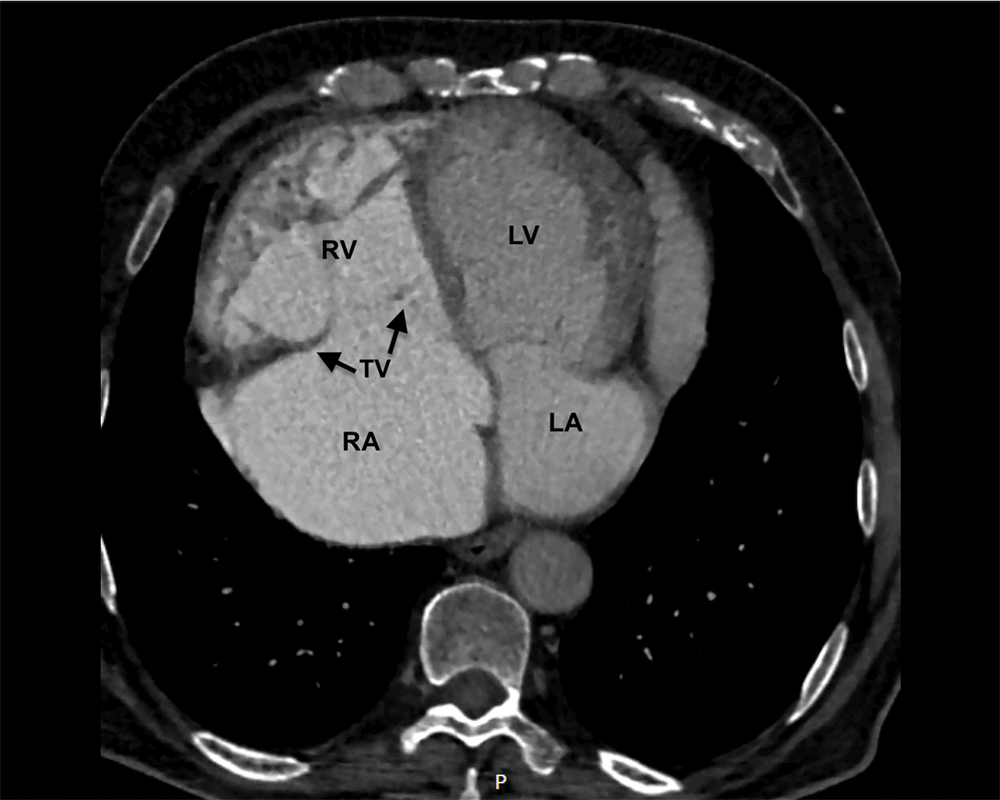

Four months before admission, he was admitted to the emergency department of our institution due to acute right heart failure exacerbation. During the in-hospital stay, echocardiography was performed and revealed situs solitus, dextrocardia, and severe tricuspid regurgitation due to a mild form of Ebstein anomaly (type A by Carpentier classification) with incomplete delamination of the septal leaflet and malcoaptation due to severe annular and right ventricle and right atrium dilatation in long-standing disease (Fig. 1). There was no displacement of the inferior leaflet hinge point and no significant rotation of the tricuspid valve, but the septal leaflet offset was apically displaced by 21 mm (indexed by body surface area (BSA) 9 mm/m2) in comparison with the mitral valve, which is slightly above the cut-off value for establishing Ebstein anomaly diagnosis (Fig. 1). Additionally, echocardiography showed an abnormal pulmonary valve with moderate pulmonary regurgitation, mild pulmonary stenosis, and severely dilated main pulmonary artery and pulmonary artery branches (Fig. 2). The patent foramen ovale with left-to-right shunting was established as well. On the ECG atrial flutter and left bundle branch block were observed. Right heart catheterization showed an absence of pulmonary hypertension (mean pulmonary artery pressure 17 mmHg, wedge pressure 22 mmHg, Rp/Rs 0.07, pulmonary vascular resistance 3 Wood units) and confirmed patent foramen ovale with left-to-right shunting. The peripheral oxygen saturation was 94% without oxygen supplementation. Chest CT scan showed a large main pulmonary artery aneurysm, 10.4 cm in diameter, with dilated left and right pulmonary arteries (2.8 and 3.2 cm in diameter, respectively) (Figs. 3 and 4).

Figure 4: Chest CT scan shows dextrocardia and severely dilated right atrium and ventricle (RV–right ventricle; RA–right atrium, LV–left ventricle, LA–left atrium, TV–tricuspid valve (black arrows))